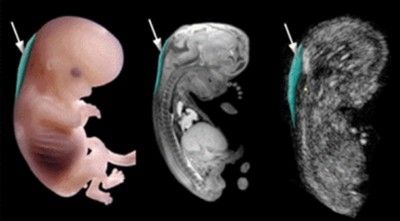

Правильный расчет срока беременности имеет большое значение не только для определения предполагаемой даты родов, но и для планирования первого скрининга. К началу 11-й недели завершается эмбриональный этап развития, когда формируются органы, конечности, лицевые кости и нервная система.

Скрининг первого триместра беременности осуществляется к моменту завершения этого срока. Максимальный срок для проведения исследования составляет 13 недель и 6 дней.

Проведение скрининга до указанных сроков нецелесообразно, так как результаты могут быть искажены, что не позволит выявить возможные патологии.

Толщина воротникового пространства (ТВП) является ключевым показателем риска хромосомных аномалий. Воротниковое пространство представляет собой скопление подкожной жидкости, находящейся между кожей и костной тканью.

Для того чтобы правильно провести первый скрининг во время беременности и избежать неверных результатов, необходимо учитывать квалификацию врача-гинеколога. Важно точно определить срок беременности, который требуется для данного обследования. На 10-й неделе размер плода недостаточен для проведения тестирования, тогда как к 14 неделям размеры шейной складки начинают физиологически уменьшаться.

Для получения наиболее точных результатов необходимо соблюдать следующие условия:

- Корректное определение срока беременности. Он устанавливается на основе размеров копчико-теменной зоны.

- Боковое положение эмбриона способствует более точному определению результатов теста. Если плод не может занять правильное положение, может потребоваться применение трансвагинального метода исследования.

- Квалификация врача. Петельки пуповины и амниотические полости могут привести к ложноположительным результатам. Опытный специалист, работающий на высокоточном оборудовании, должен исключить возможность ошибок.

Полную информацию о состоянии эмбриона можно получить не только с помощью УЗИ, но и благодаря анализу биохимических маркеров. Результаты тестов могут варьироваться в зависимости от срока беременности. Нормальные значения для воротникового пространства должны находиться в диапазоне от 0,7 мм до 4 мм.

Увеличение толщины ТВП служит основанием для проведения более глубокого обследования, которое включает анализ околоплодных вод, плаценты и пуповинной крови.